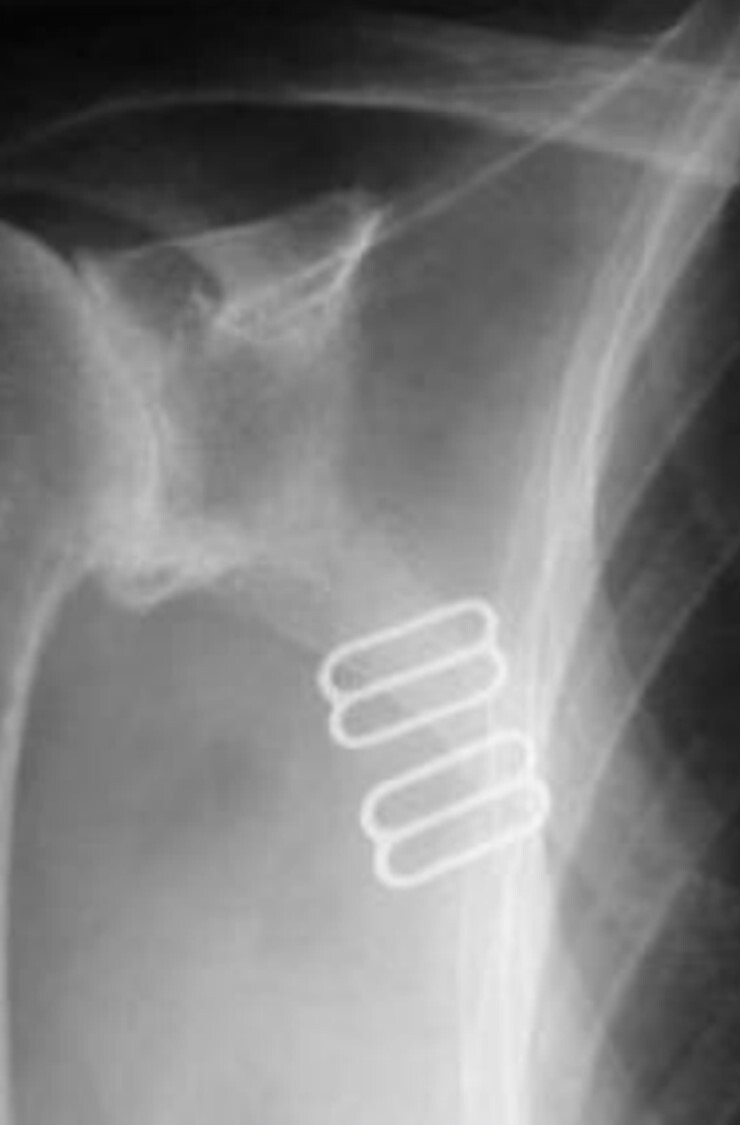

Q

Aside from the surgically implanted hardware, what artifact is seen in the attached image?

A

Quantum mottle from underexposure